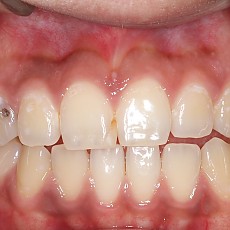

시술전후사진 6 페이지

Total 189건 6 페이지